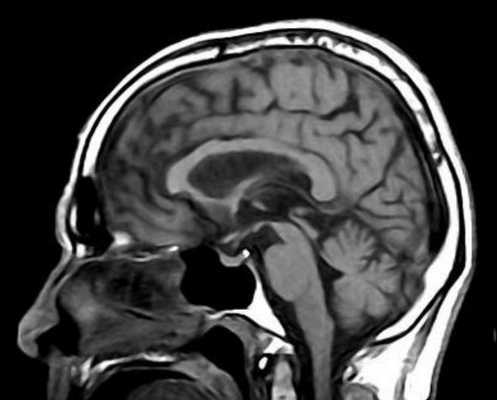

МРТ головного мозга выявляет скопление гемосидерина. Наиболее чувствительны градиентные Т2-взвешенные МРТ. Часто отмечается атрофия червя мозжечка, особенно, видимая хорошо на сагиттальных Т1-взвешенных МРТ.

МРТ головного мозга. Т2-взвешенная аксиальная МРТ через ствол. Тонкое темное кольцо гемосидерина вокруг ствола и в мозжечке. Сидероз головного мозга.